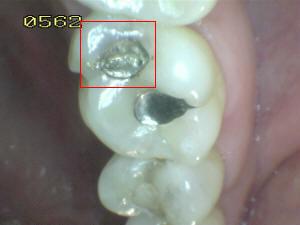

Sistema Internacional para la Detección y Evaluación de Caries (ICDAS)

¿Determine los códigos pertinentes a cada imagen?

Click en el hipervínculo: Para comparar el resultado de su diagnóstico